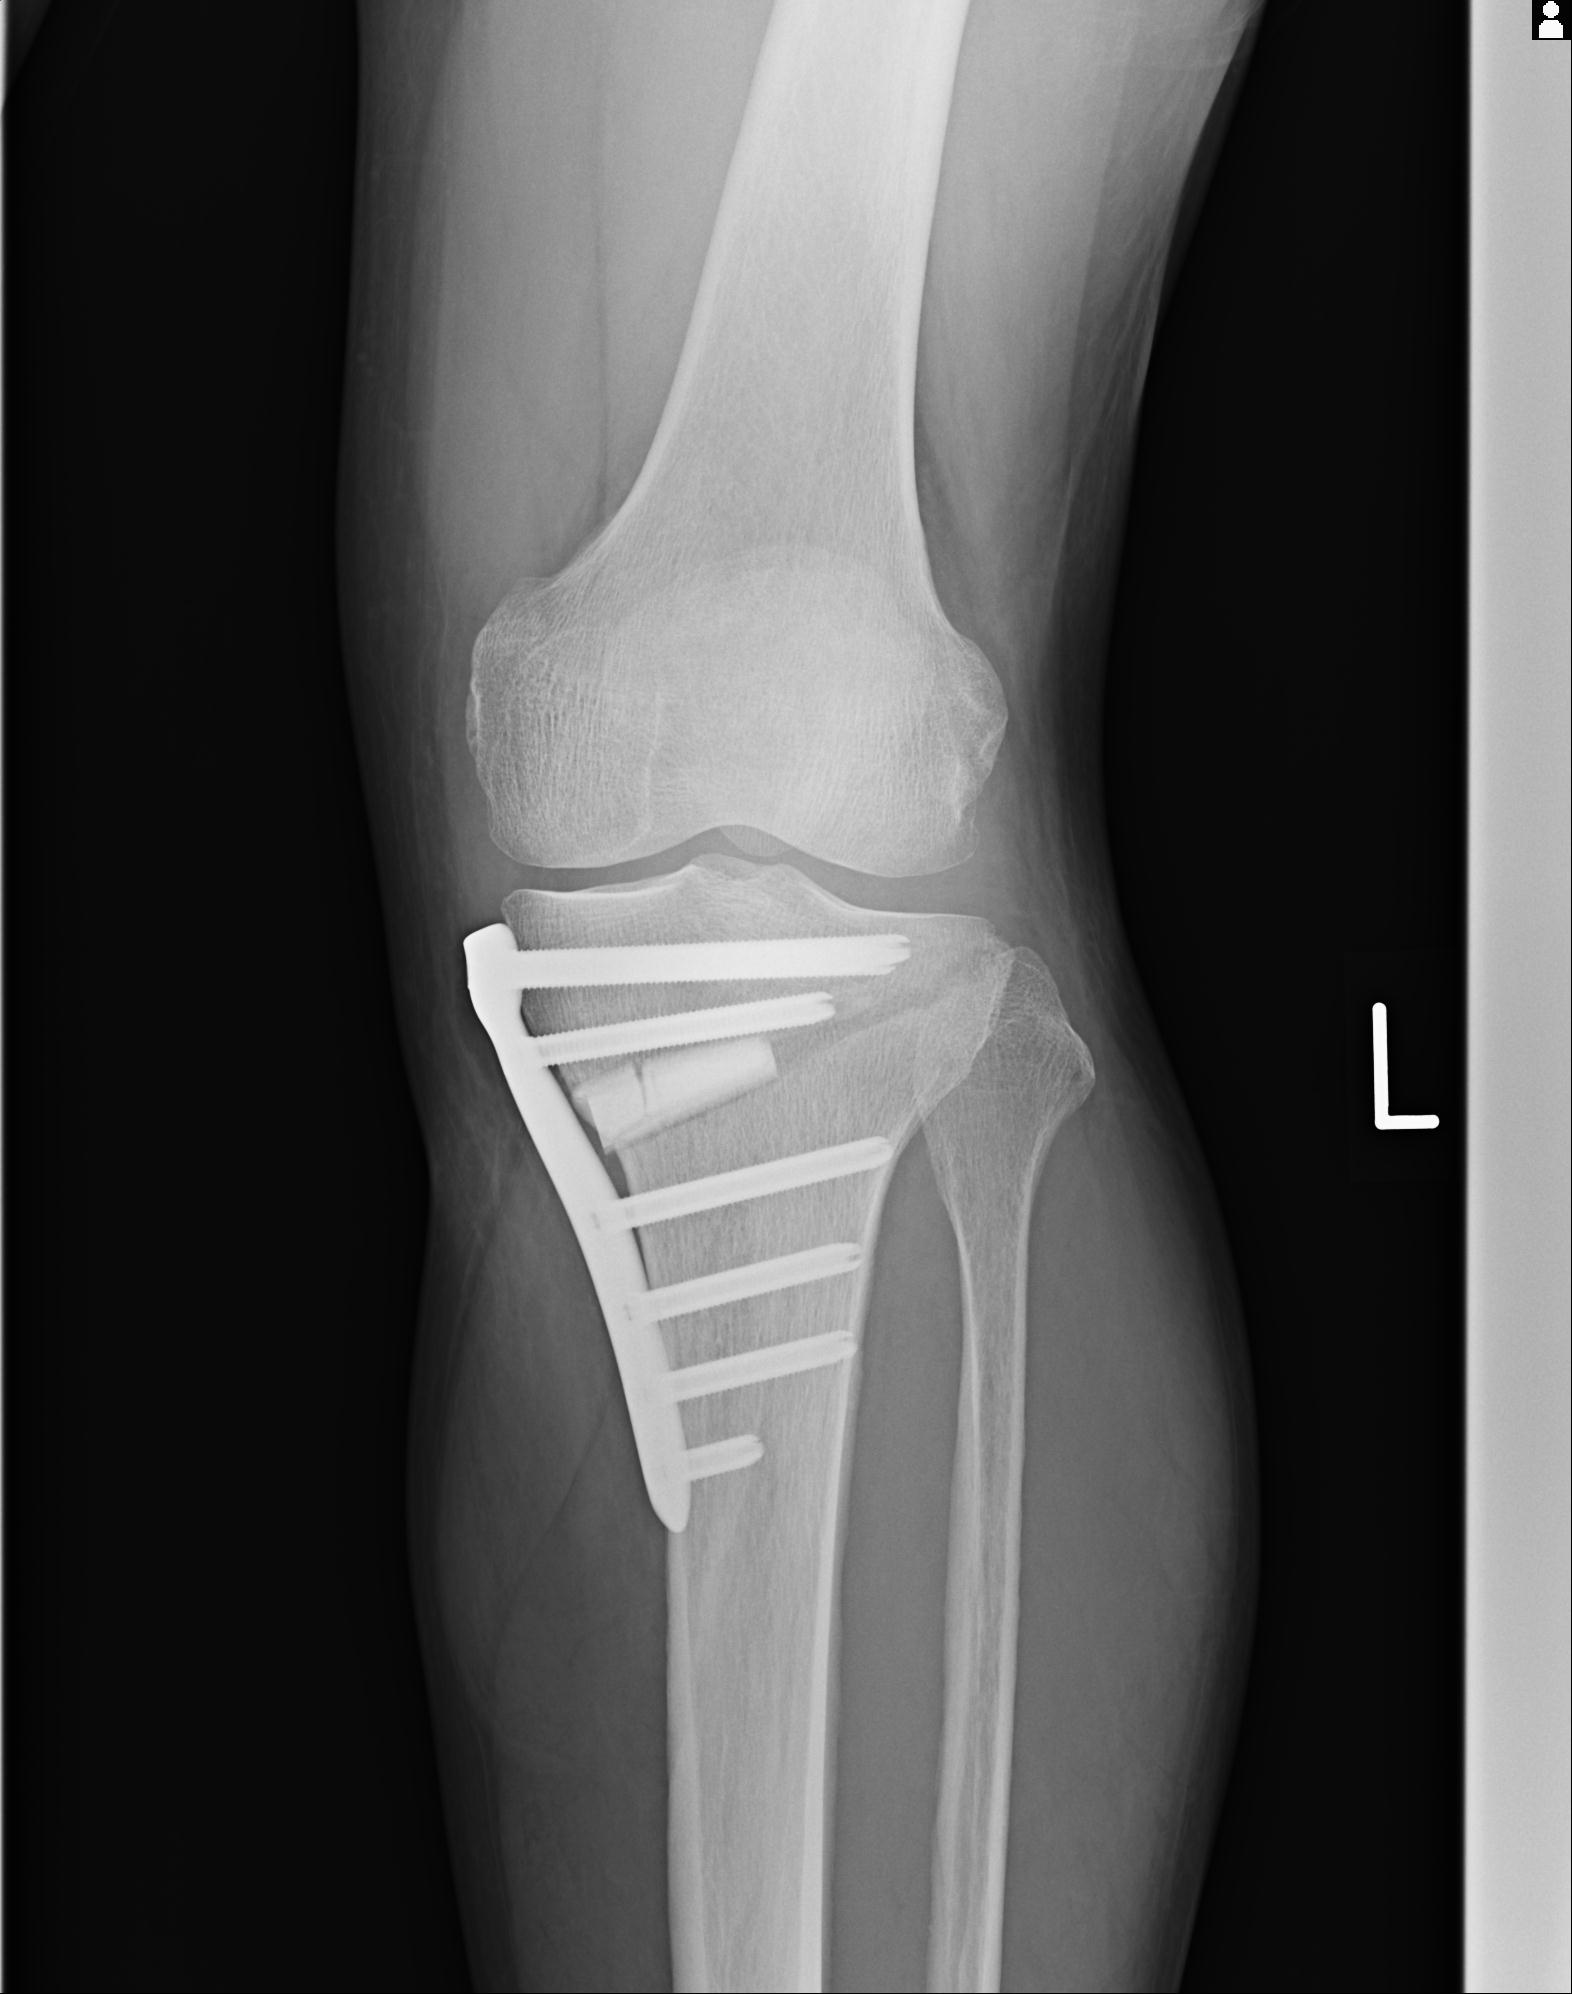

91983 11/16 左膝 2R 11/18 2R 55歳男性 脛骨骨切り術